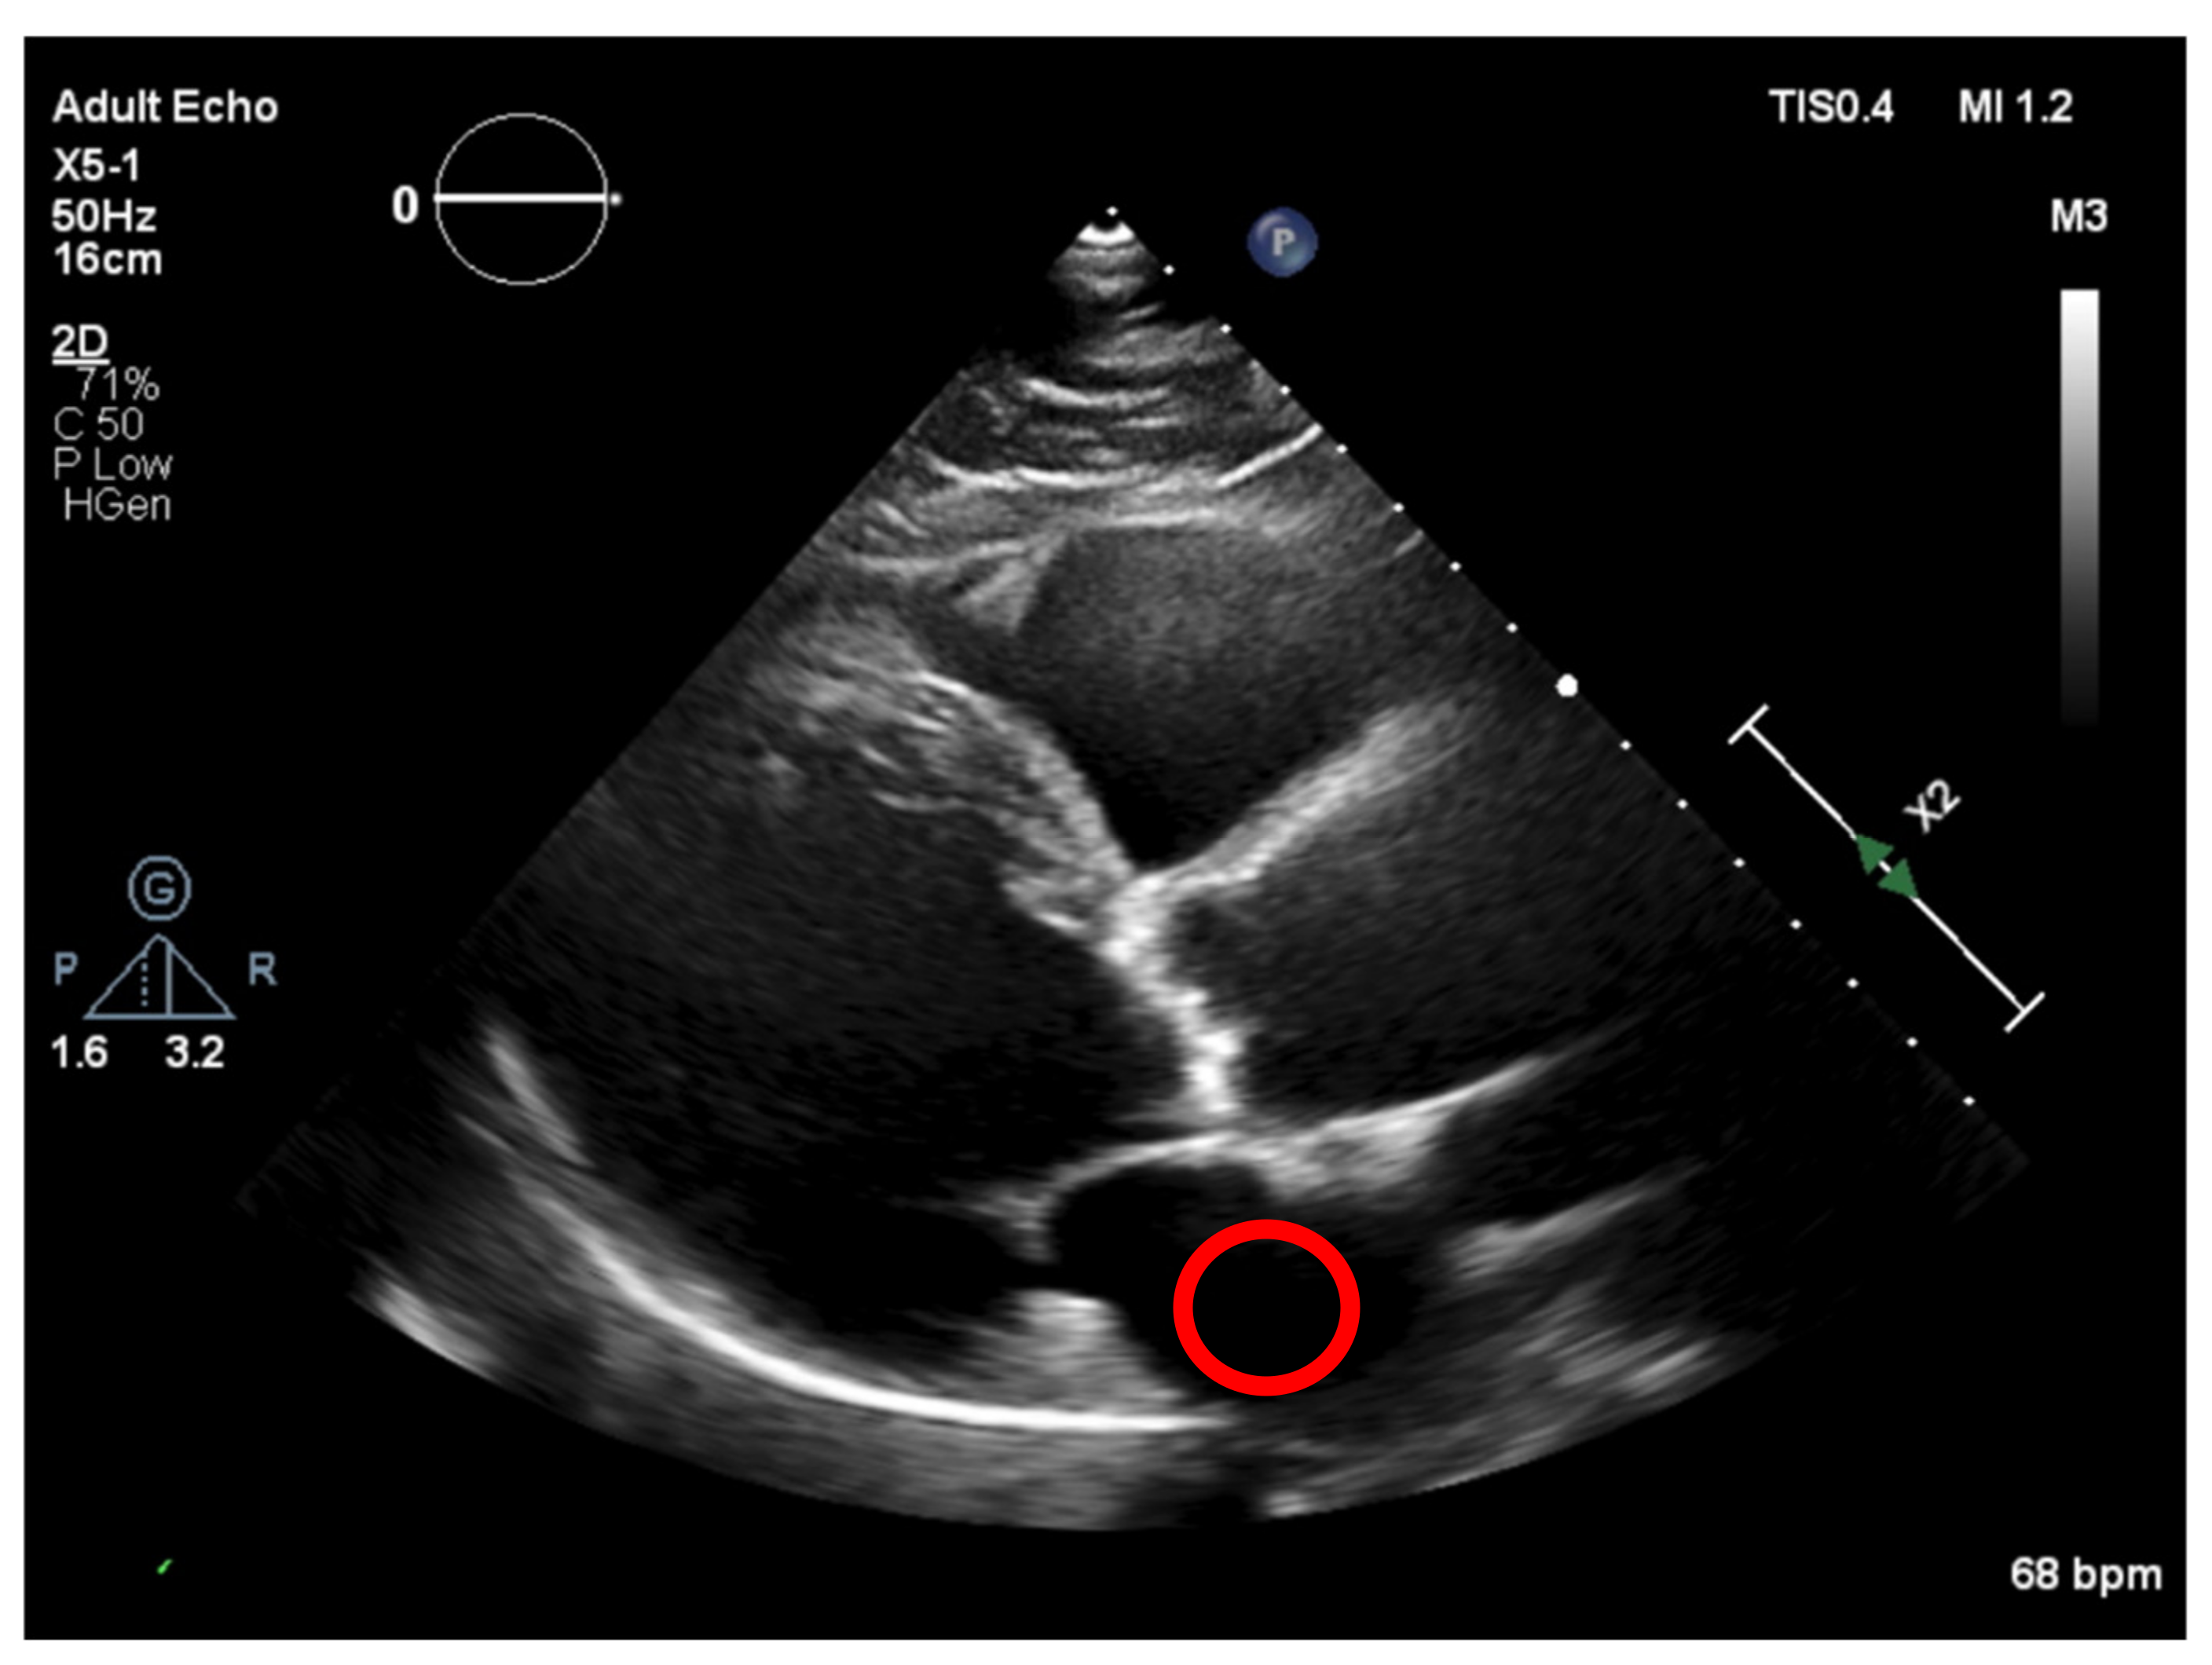

To deal with some natural constraints in terms of noise that characterize echocardiography imaging, particularly the process of sampling still images from the echocardiography video, different blurring treatments were performed to clean some of the image’s noise due to the echocardiography’s motion. Blurring an image will average rapid changes in the different pixel intensities, and this corresponds to a low-pass filter applied to the image [23], which removes noise while leaving the majority of the image structures still present in the image as depicted in Figure 4.

As it can be seen from Figure 4, when the Blur = 11 (experimentally adjusted with trial and error)), it can be easily identified, visually, in the regions where there is a presence of calcium (identified by the red circles). On this operation the central element of the image is replaced by the median of all the pixels in the kernel region, where the 11 means that it takes into consideration a kernel of 11 by 11.

Figure 4. Echocardiography image with four levels of blurring applied—the red circle represents our ROI where the aortic valve is located.